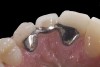

(5.) Double-wing metal resin-bonded bridge replacing lateral incisor (lingual view).

Figure 5